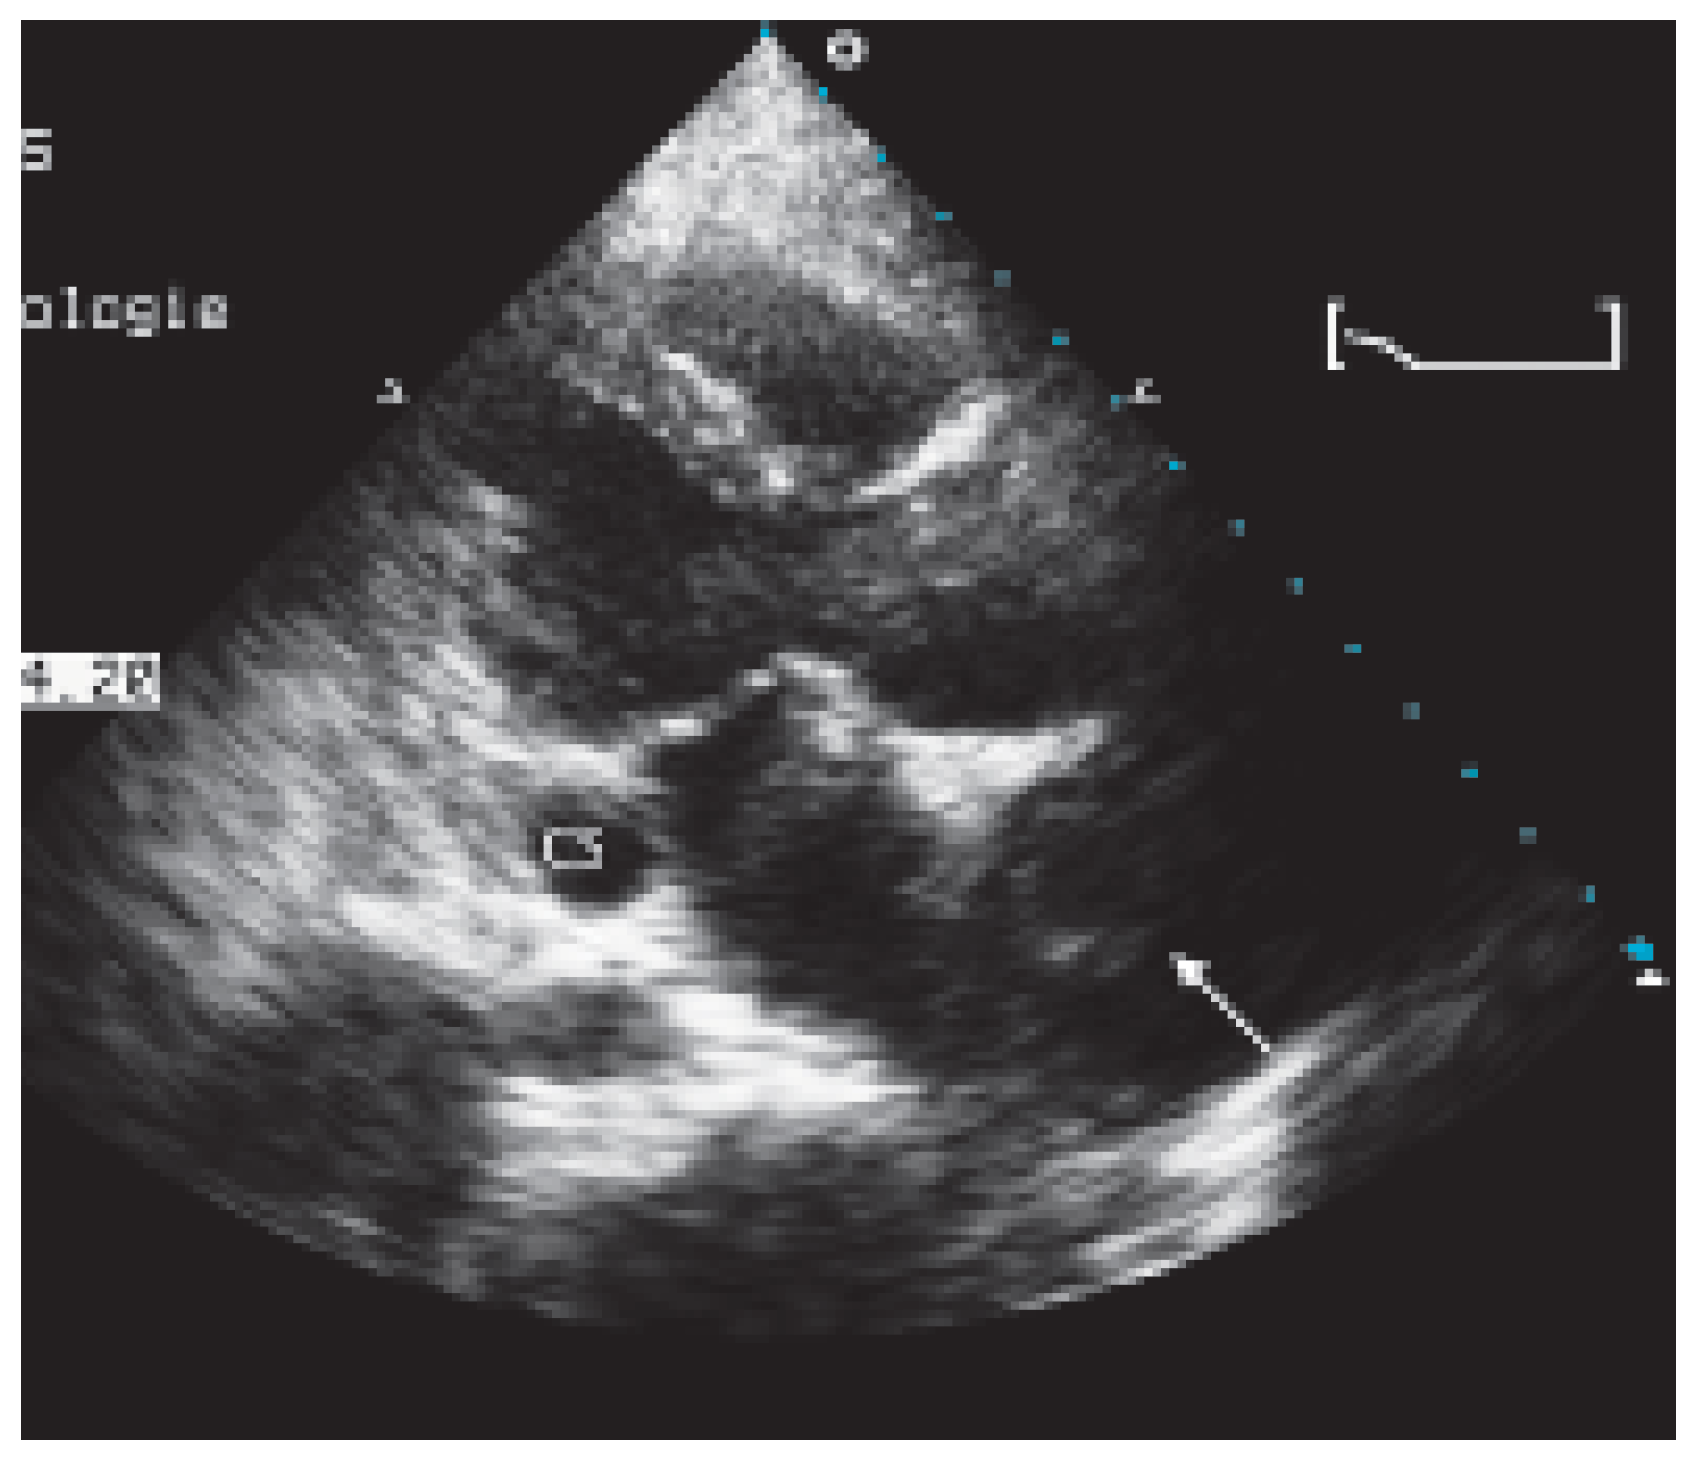

Case report